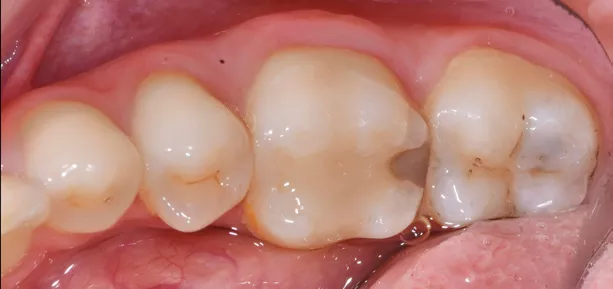

Fig. 1 Initial situation.

A young patient visited our clinic, complaining of sensitivity in the right posterior region. Upon clinical examination, we identified a defective restoration on tooth 46 and detected caries on tooth 47. After discussing the treatment options, we decided to proceed with direct restorations for both teeth, and the patient agreed to move forward with the plan.